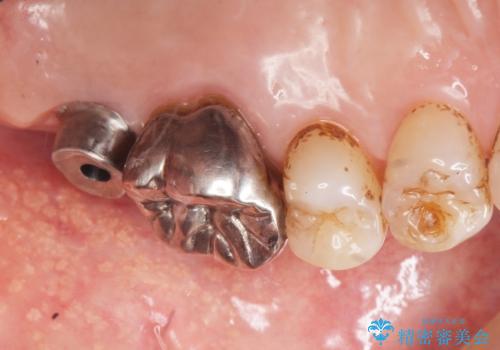

上顎洞が近接しており上顎骨の厚みが薄いことから、ソケットリフト(上顎洞底挙上術)をインプラント埋入と同時に行いました。

奥歯でしっかりと咬むことができるようになり、ご満足頂けました。

初診時から治療終了時までのレントゲンをお見せして説明差し上げたところ、「お~!骨ができている!」と喜んで下さいました。

ソケットリフトにより上顎洞底を挙上し骨造成することにより、骨の厚みが薄い部分でもインプラントが可能になります。

インプラントの種類:ストローマン BLT

クラウンの種類:メタルボンドクラウン エコノミー